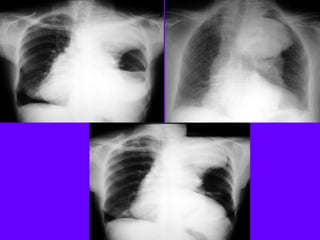

Necrotizing Pneumonia / Lung Abscess / Aspiration

Superior segment RLL dense pneumonia

Progression / Cavity